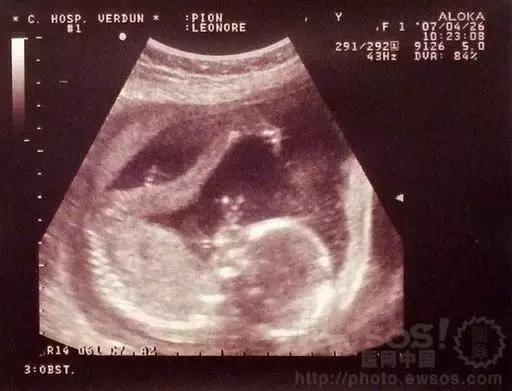

B超技术实现了人体的无损“透视”,为人类的诊疗保健带来了质的飞跃。尤其对产科更解决了过去许多难以检出的疑难问题。如既能对胎盘定位、羊水测量,又能对单胎多胎、胎儿发育情况及有否畸形和葡萄胎等作出早期诊断。所以广泛应用于现代优生优育医学工程中。

孕18-20周,核对孕龄,判断胎儿生长发育情况。这一阶段胎儿B超多项指标误差较小,可以测量胎儿的各个部位,如胎头大小、胎臀长度,测定胎头的双顶径、头围、腹围及胎儿股骨的长度等。

第孕28-30周,此时做B超目的主要是排畸,了解胎儿发育情况,还能对胎儿的位置及羊水量有进一步的了解。

孕37-40周,目的是确定胎位、胎儿大小、胎盘成熟度,有无脐带缠颈等,进行临产前的最后评估。